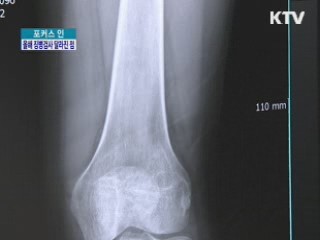

올 첫 '징병검사'…무엇이 달라졌나

올해 첫 징병검사가 어제부터 전국에서 시작됐습니다.

정부가 병역비리를 원천적으로 차단하기 위해 징병검사 기준을 대폭 강화했는데요.

바뀐 징병검사 제도, 어떤 것들이 있는지 취재기자와 함께 자세히 알아보겠습니다.